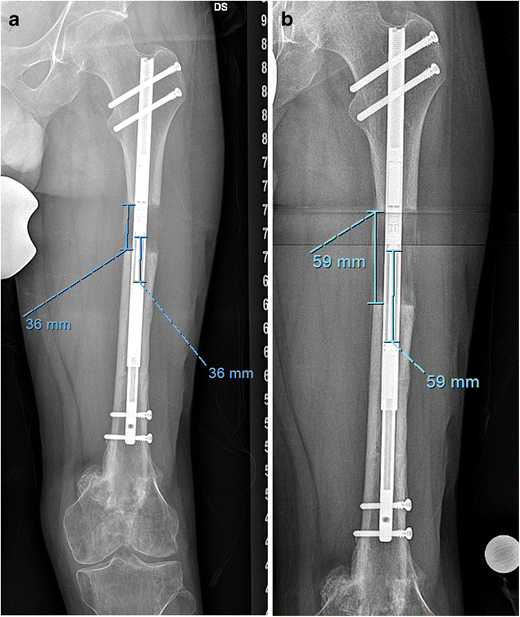

(a) The lengthening is complete and the limb length is checked. The Magnetic Limb Lengthening The magnetic intramedullary lengthening nail can be predistracted and used to compress bony interfaces to assist in the healing of nonunions. Interaction between magnets in the device and an erc allow for precise, adjustable. We use the best tools available today including precice® motorized magnetic lengthening and compression nails, automated hexapod external fixation, osseointegration limb. In most cases, the femur,. Magnetic Limb Lengthening.